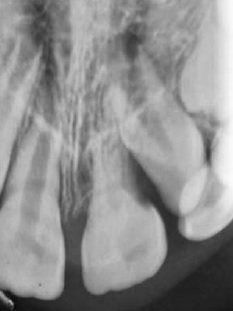

After 3 months of follow-up, the tooth presented a slight metallic sound to the percussion test, and the crown’s color was normal. No signs of ankylosis were observed in the periapical radiograph (Figure 4), and the tooth continued non-responsive to the cold test. In the fourth month of follow-up, the tooth exhibited slight mobility, but no other signs or symptoms were observed. Six months after the trauma, a positive response to the sensibility test was verified. After 9 months, the percussion test suggested ankylosis. The color of the tooth remained stable (Figure 5). A cone beam computed tomography (CBCT) suggested a formation of calcified tissue in the root’s apical third (Figure 6). At the 1-year follow-up, a periapical radiograph showed external root resorption in the cervical third of 21 (Figure 7). The patient did not exhibit fistula, gingivitis, pain, or any change in tooth color. The tooth was in infra-occlusion, and the clinical crown was 7 mm long.

Figure 4 Periapical radiograph three months after the trauma showing no signs of ankylosis or root resorption.